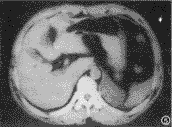

慢性血肿:形态规则,密度不均匀的囊状病变,单房,囊内可见稍高密度的小血块影。壁厚均匀,增强见壁环形轻度强化,囊内小血块影未见强化,CT值30~45HU,部分边缘与周围脏器粘连,大小分别为5.8cm×8.0cm和6.5cm×7.8cm(图4)。

图4 慢性血肿,壁较厚的囊状包块,囊内可见稍高密度的血块影